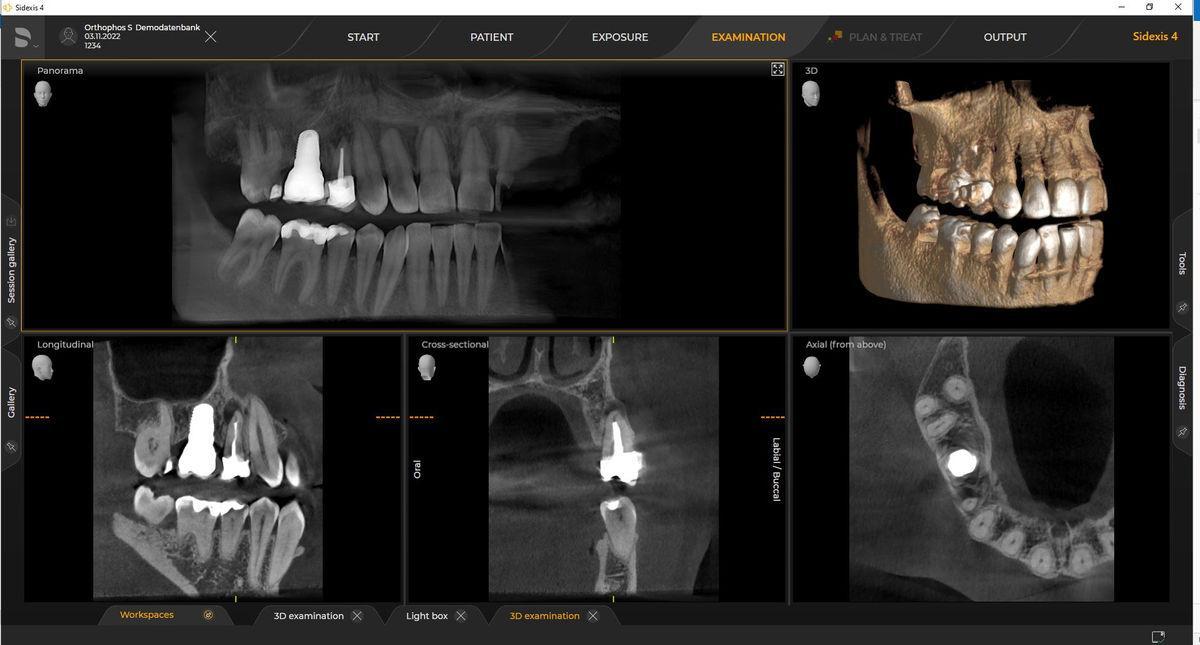

CBCT imaging technology

CBCT 3D Imaging

3D radiographic technology in dentistry has revolutionized the field by providing dentists with a comprehensive view of the patient's oral structures. This technology, primarily Cone Beam Computed Tomography (CBCT), offers three-dimensional images of teeth, soft tissue, and bone in a single scan.

Why do we use CBCT Technology?

• Improved diagnosis: CBCT scans help in detecting infections, fractures, and bone loss that may not be visible on 2D x-rays.

• Better Treatment Planning: The detailed images assist in procedures like implants, root canals, and jaw surgeries.

• Clearer Views of Nerves and Sinuses: This helps avoid complications during a surgery.

• Accurate Bone Measurements: Essential for planning dental implants.

• Reduced Radiation Exposure: 3D scans use less ionizing radiation than panoramic views and standard cephalograms.